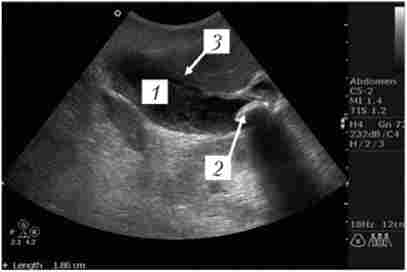

При неможливості здійснити ЕРПХГ (попередня резекція шлунка по Більрот-П, неможливість канюліровать БДС) може бути виконана черезшкірна чреспеченочнаяхолангіографія - ЧЧХГ (рис. 18.3). У хворих з механічною жовтяницею і холангітом діагностичний етап завершується лікувальним: чреспеченочной холангіо- Стома (ЧЧХС) для купірування біліарної гіпертензії, холангіту і підготовки хворого до основного етапу лікування - лапароскопічної або відкритої санації жовчних шляхів.

Черезшкірна чреспеченочнаяхолангіографія

Мал. 18.3. Черезшкірна чреспеченочнаяхолангіографія.

Видно розширені внутрішньо-і позапечінкові жовчні протоки (/), камінь холедоха (2). Контраст не надходить в ДПК